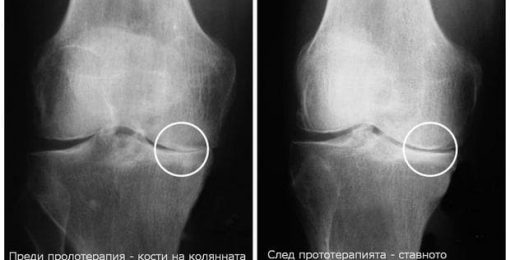

Joint and back pain can cause serious disruptions in people’s lives—from missing work to reduced mobility. Prolotherapy uses the body’s natural healing ability to alleviate chronic pain, strengthen damaged tissues, and restore function. It is a procedure in which a naturally occurring irritant is injected into the soft tissues of a damaged joint or area. This deliberate inflammation is designed to signal the body that there is a problem, so that our own bodies can cope by building new tissue. This can provide significant relief for joint or back pain.

Once activated, the body’s defenses and healing powers will begin to strengthen and repair damaged tissues. When it comes to joints, strengthening the connections in the area helps stabilize the joint and relieve pain over time.

Prolotherapy is also applicable in the area of the knee, hip and shoulder joints and connecting tissues. Indications that this kind of therapy is needed may include: sciatica, back pain, torn meniscus, distended tendons and ligaments, neck pain, rotator cuff disorders, tennis elbow, chest pain, leg pain and more. In some cases, people with chronic illnesses, such as degenerative disc disease or arthritis, may use prolotherapy to relieve the pain.